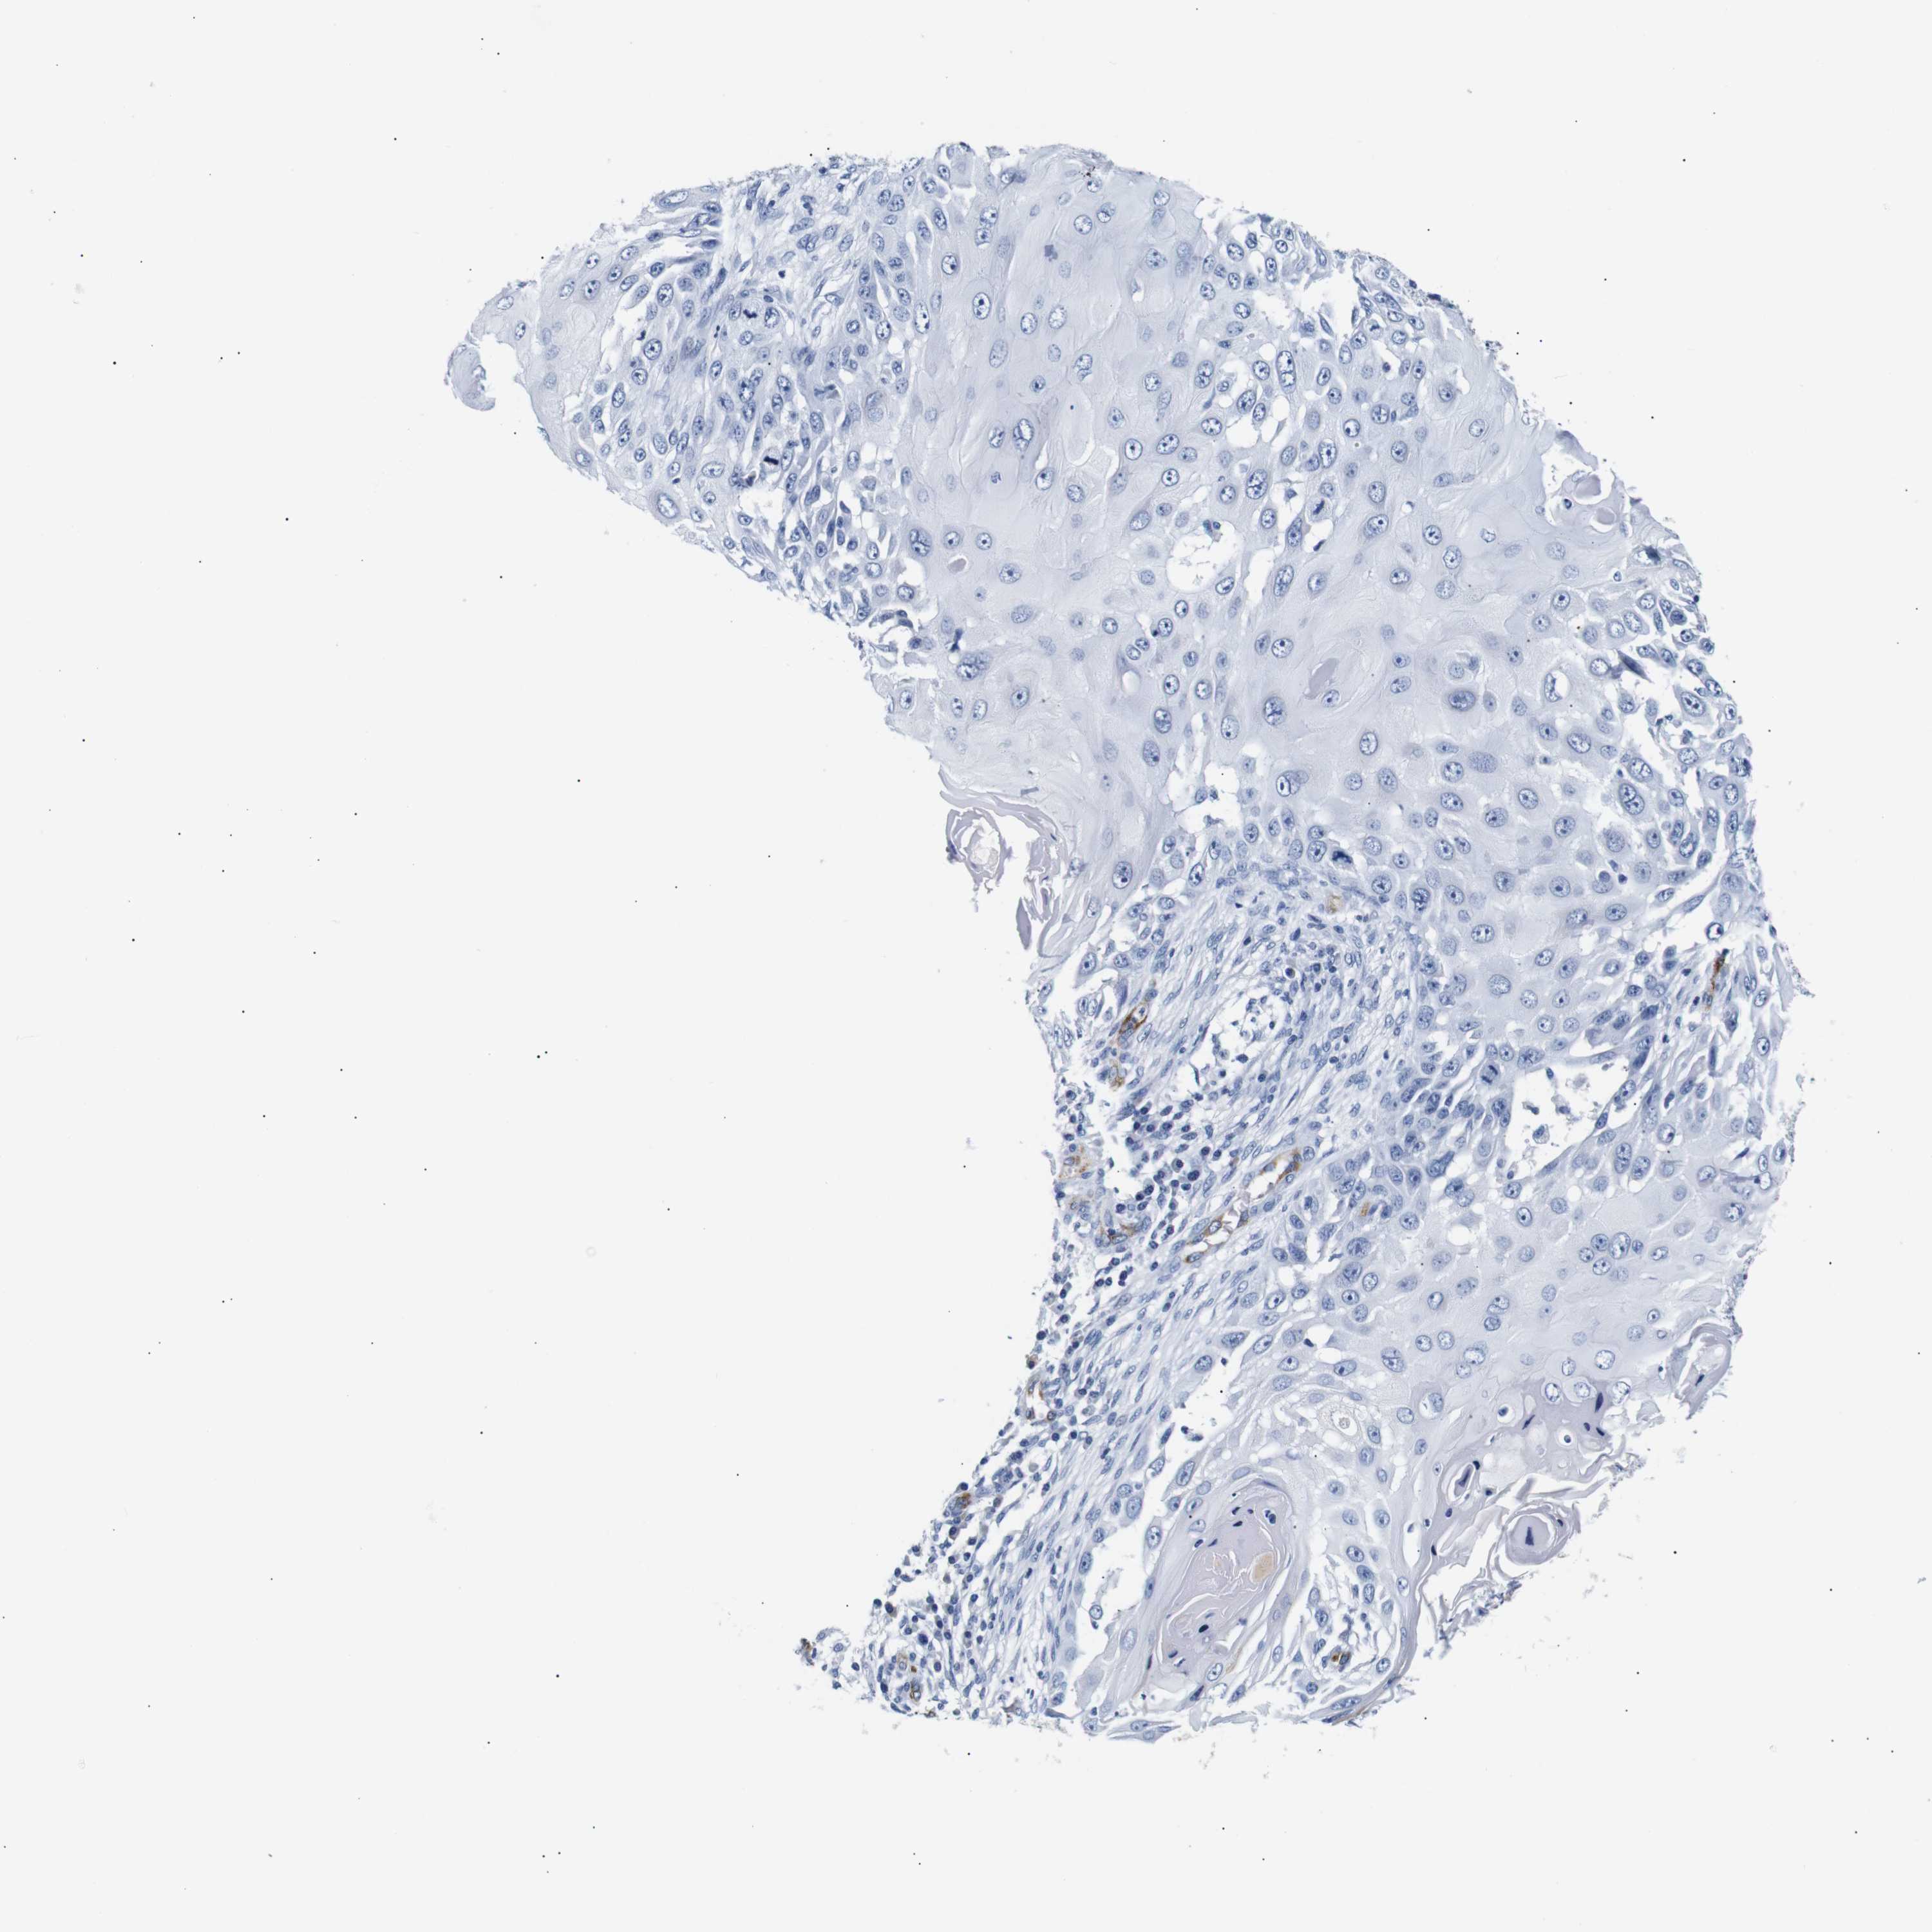

SKIN CANCER - Protein expressioni

A mouse-over function shows sample information and annotation data. Click on an image to view it in a full screen mode. Samples can be filtered based on level of antibody staining by selecting one or several of the following categories: high, medium, low and not detected. The assay and annotation is described here.

Antibody stainingi

Antibody staining in the annotated cell types in the current human tissue is reported as not detected, low, medium, or high, based on conventional immunohistochemistry profiling in selected tissues. This score is based on the combination of the staining intensity and fraction of stained cells.

Each image is clickable and will lead to virtual microscopy that enables deeper exploration of all samples and also displays staining intensity scores, fraction scores and subcellular localization as well as patient and tissue information for each sample.

Antibody HPA005895

Antibody CAB013536

Squamous cell carcinoma, NOS

Basal cell carcinoma